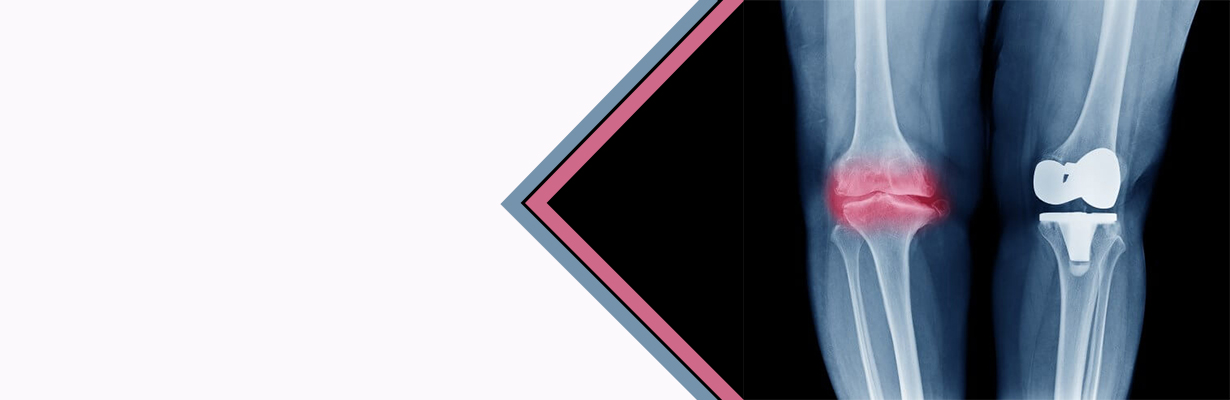

In this video, Dr. Ramneek Mahajan, Director - Orthopedics & Joint Replacement, Max Smart Super Specialty Hospital, New Delhi will discuss about total knee replacement in this video. He explains that the total knee replacement is done when the disease process has occurred in more than one compartment. He further states that there is a tibial, femoral component and a base plate made up of polyethylene and sometimes occasionally the patellar button is also replaced. If the patella is not involved then it is not replaced.